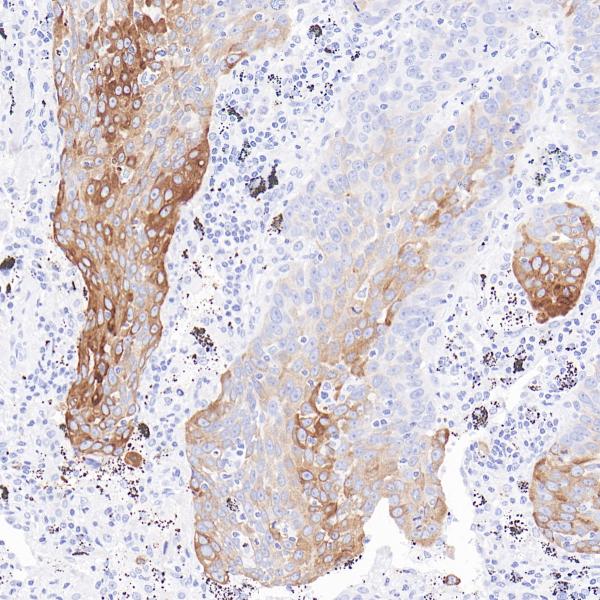

HER2

BP6020